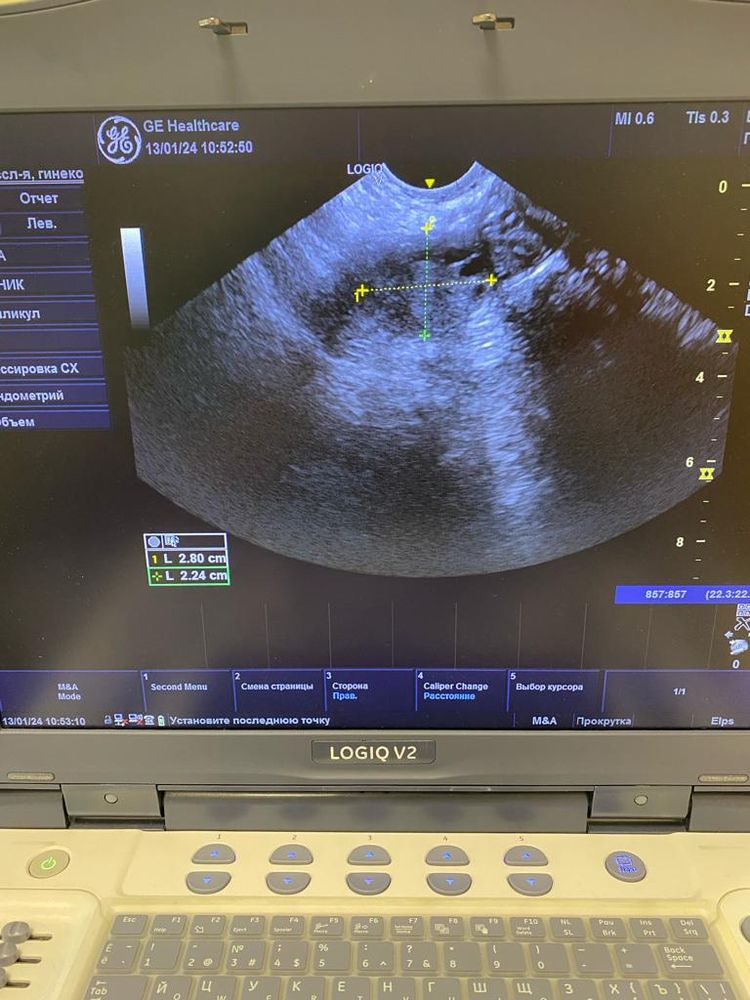

Юлия , Изображение Изображение Изображение Изображение Изображение

Ольга, по этим снимкам овуляция не вот вот. А до нее еще как минимум неделя от этого УЗИ. Фолликулы до 10 мм. И нет доминанта

Ольга, не нужны снимки, нужен протокол УзИ. Описание яичников, срез, ДФ, эндометрий. Врач узи в нескольких проекция смотрит. Я как врач, на этих снимках не вижу ДФ, фолликулы до 10 мм.. Поэтому вообще-то говорить что была овуляция сложно. Сейчас делать УЗИ нет смысла. Ждите менструацию, она начнется со дня на день. Делайте УЗи уже в след цикле в динамике, по мере роста ДФ и подтверждайте овуляцию через 7 дней после ее наступления и берите протоколы УЗИ. Сейчас мы с Вами просто гадаем на кофейной гуще.